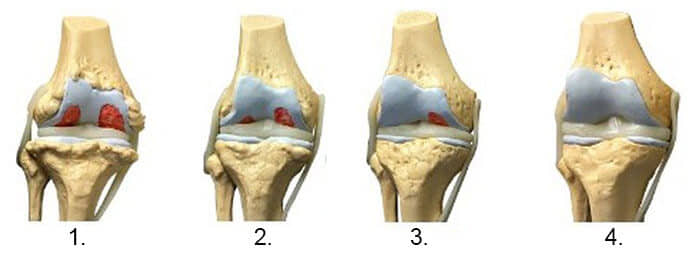

1. Nedostatak hranjivih tvari u zglobu.

Hrskavično tkivo je uništeno.

2. Obnova

hrskavičnog tkiva u zglobu nakon 2 sedmice upotrebe gele

Nautubone.

3. Obnova hrskavičnog tkiva

zgloba nakon 3 sedmice upotrebe gele Nautubone.

4.

Zdrav zglob nakon jednog kursa gele Nautubone.

- Snimak ispod pokazuje tipičnu sliku oporavka zgloba koljena.

- Uz Nautubone možete liječiti svoje bolesti kod kuće za mjesec ili dva. Nautubone ne hladi i ne anestetizira, nego "restartuje" cijelo na ćelijskom nivou. Eliminira uzrok same bolesti i obnavlja zglobove na njihovo početno, normalno stanje.